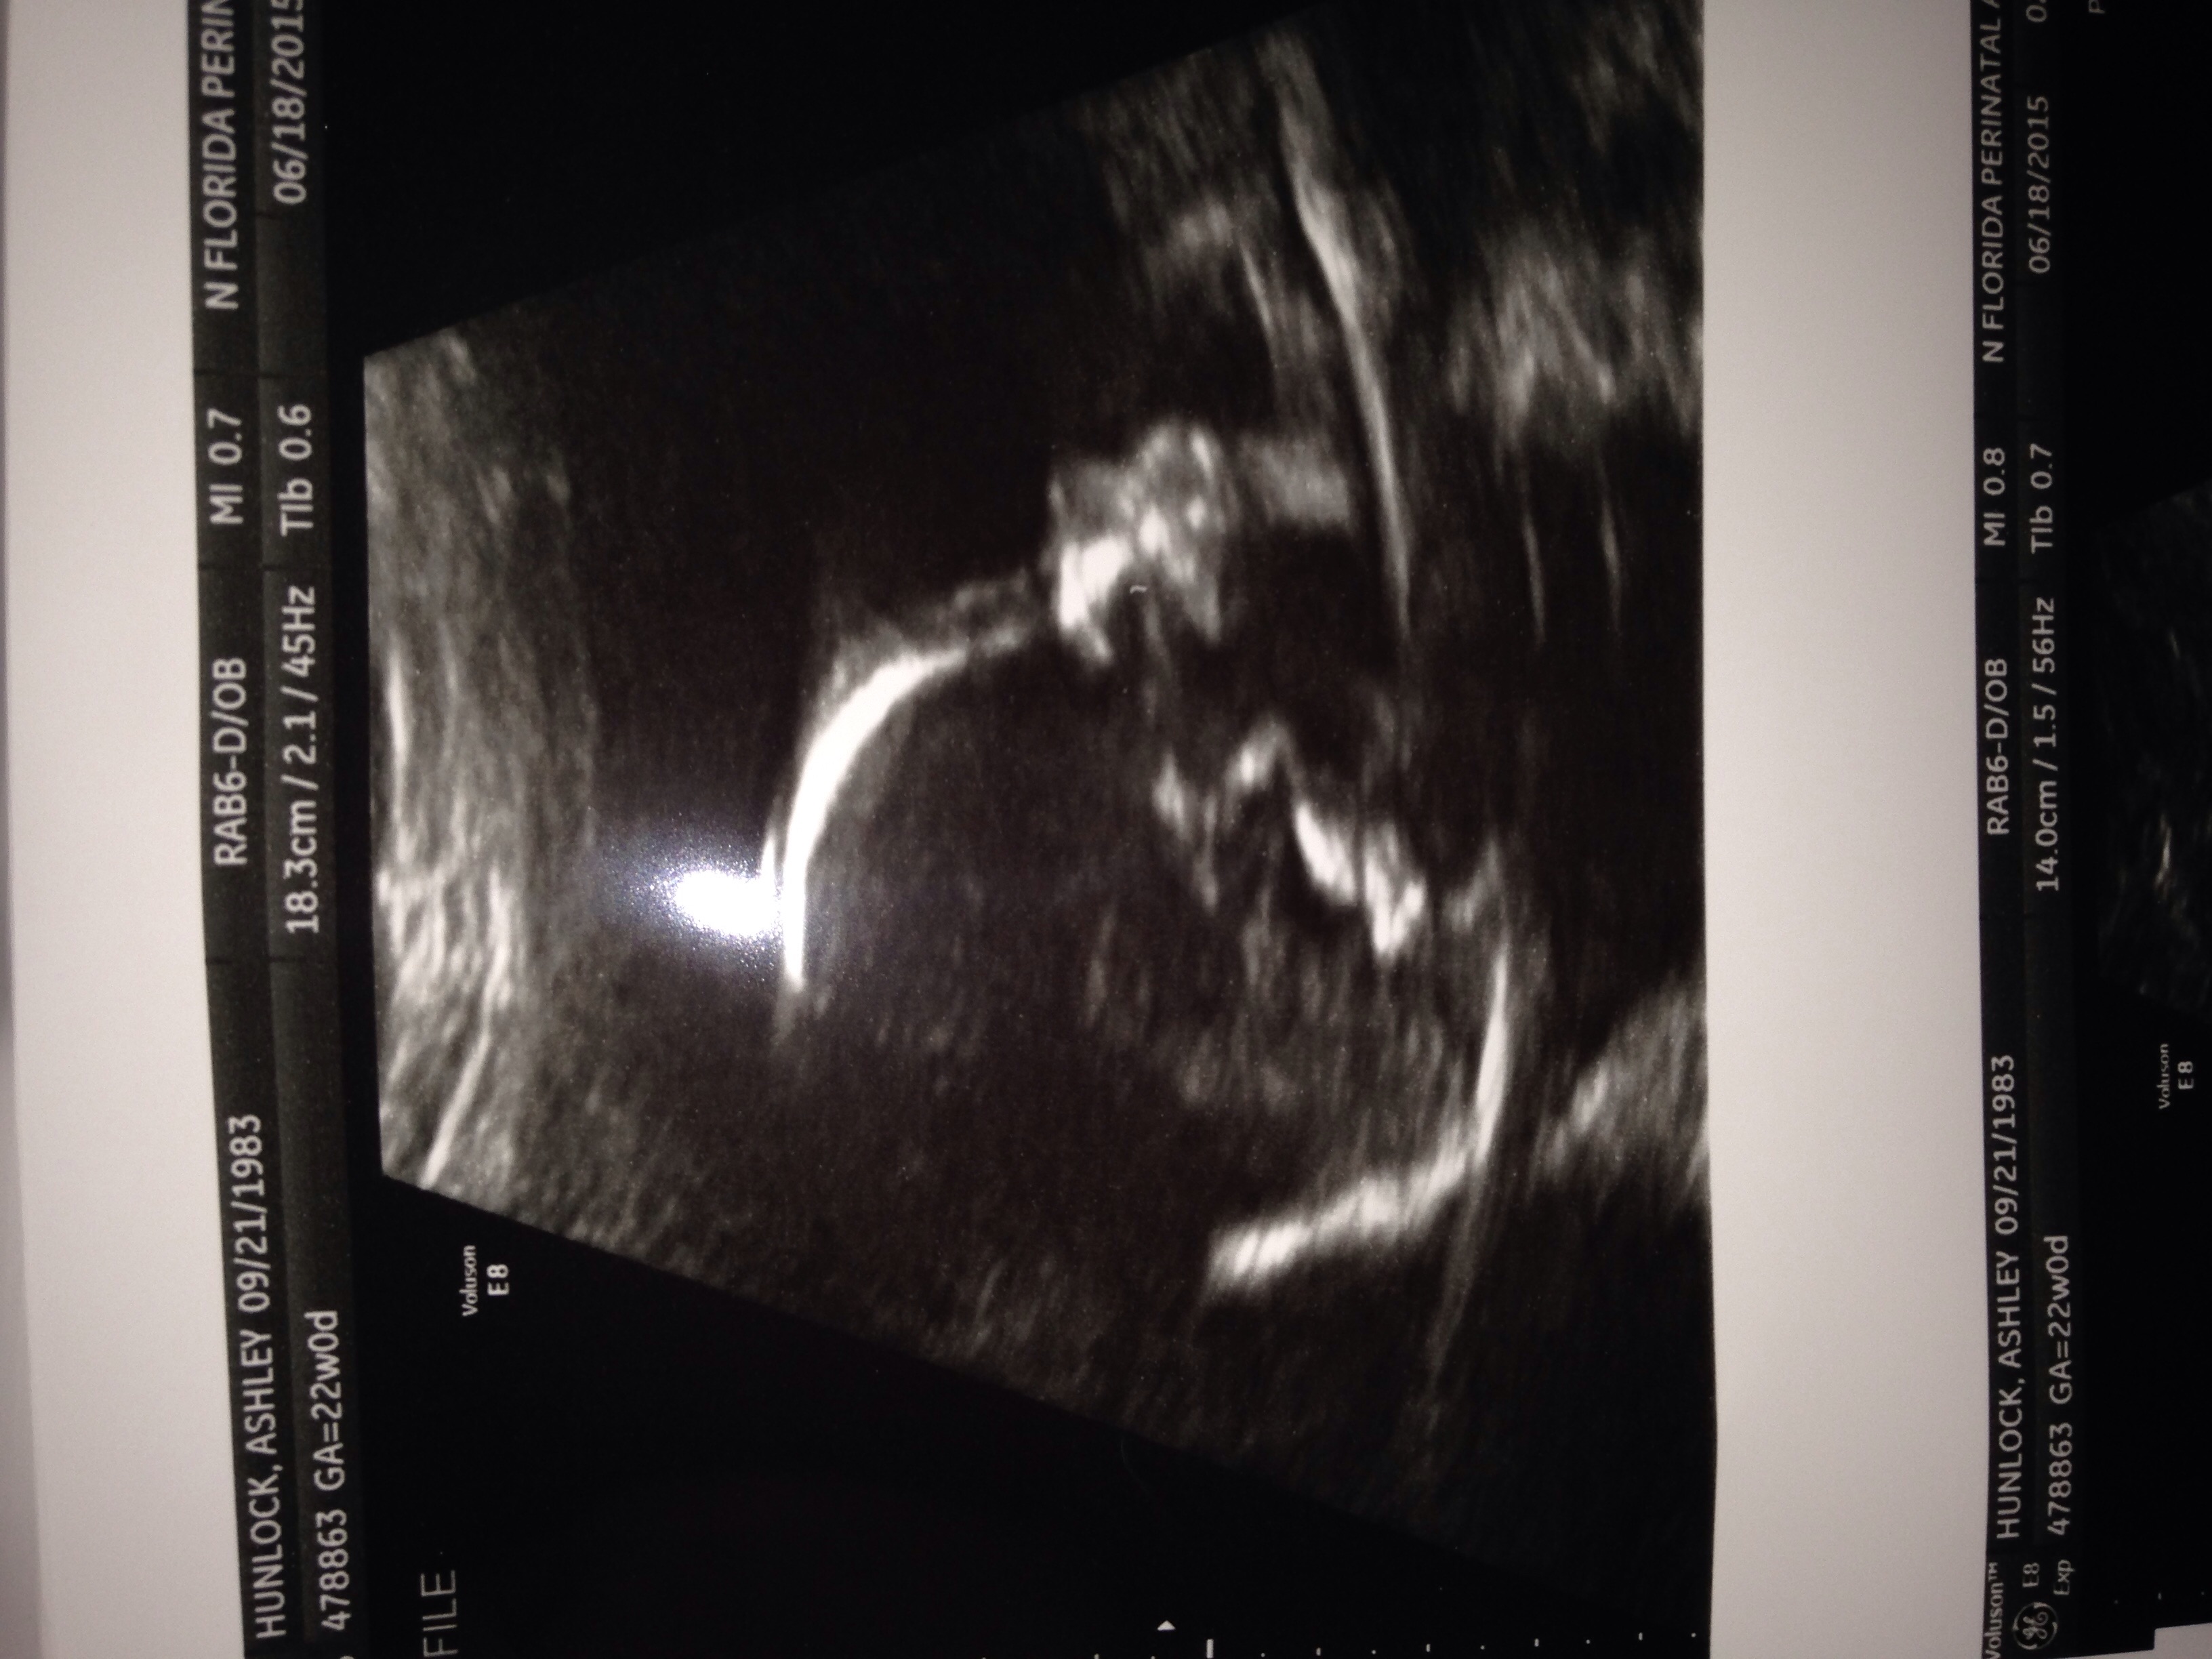

Single Umbilical Artery

At my 20 week ultrasound I found out that the umbilical cord only has one artery instead of the normal two. I've looked around and saw it could increase the risks of kidney and heart disease for baby. I go see a specialist on the 18th so I'm not stressing too bad right now. Just curious if any of you other mommas may have experienced this in a previous pregnancy or currently experiencing?

They found the same thing at our 20 week scan. They said it occurs in about 2 percent of babies and that the main concern is are they growing enough. But at the same appt they told us he's measuring in the 80th percentile so I'm not too worried. We've already had our genetic testing and have super low risk for genetic abnormalities so that's not a big concern either. We have another ultrasound scheduled at 28 weeks to check growth but that's all.